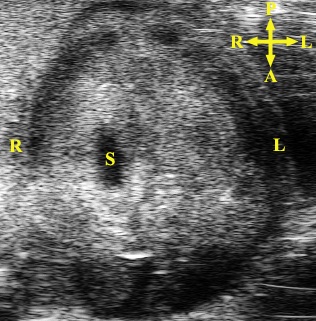

Caption Ultrasound imaging reveals a right-sided stomach (S)